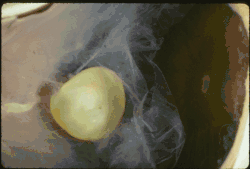

Ectopia lentis in Marfan syndrome: Zonular fibers are seen. | |

In Marfan syndrome, the health of the eye can be affected in many ways, but the principal change is partial lens dislocation, where the lens is shifted out of its normal position.[17] This occurs because of weakness in the ciliary zonules, the connective tissue strands which suspend the lens within the eye. The mutations responsible for Marfan syndrome weaken the zonules and cause them to stretch. The inferior zonules are most frequently stretched resulting in the lens shifting upwards and outwards, but it can shift in other directions as well. Nearsightedness (myopia), and blurred vision are common due to connective tissue defects in the eye.[18] Farsightedness can also result particularly if the lens is highly subluxated. Subluxation (partial dislocation) of the lens can be detected clinically in about 60% of people with Marfan syndrome by the use of a slit-lamp biomicroscope.[18] If the lens subluxation is subtle, then imaging with high-resolution ultrasound biomicroscopy might be used.[19]